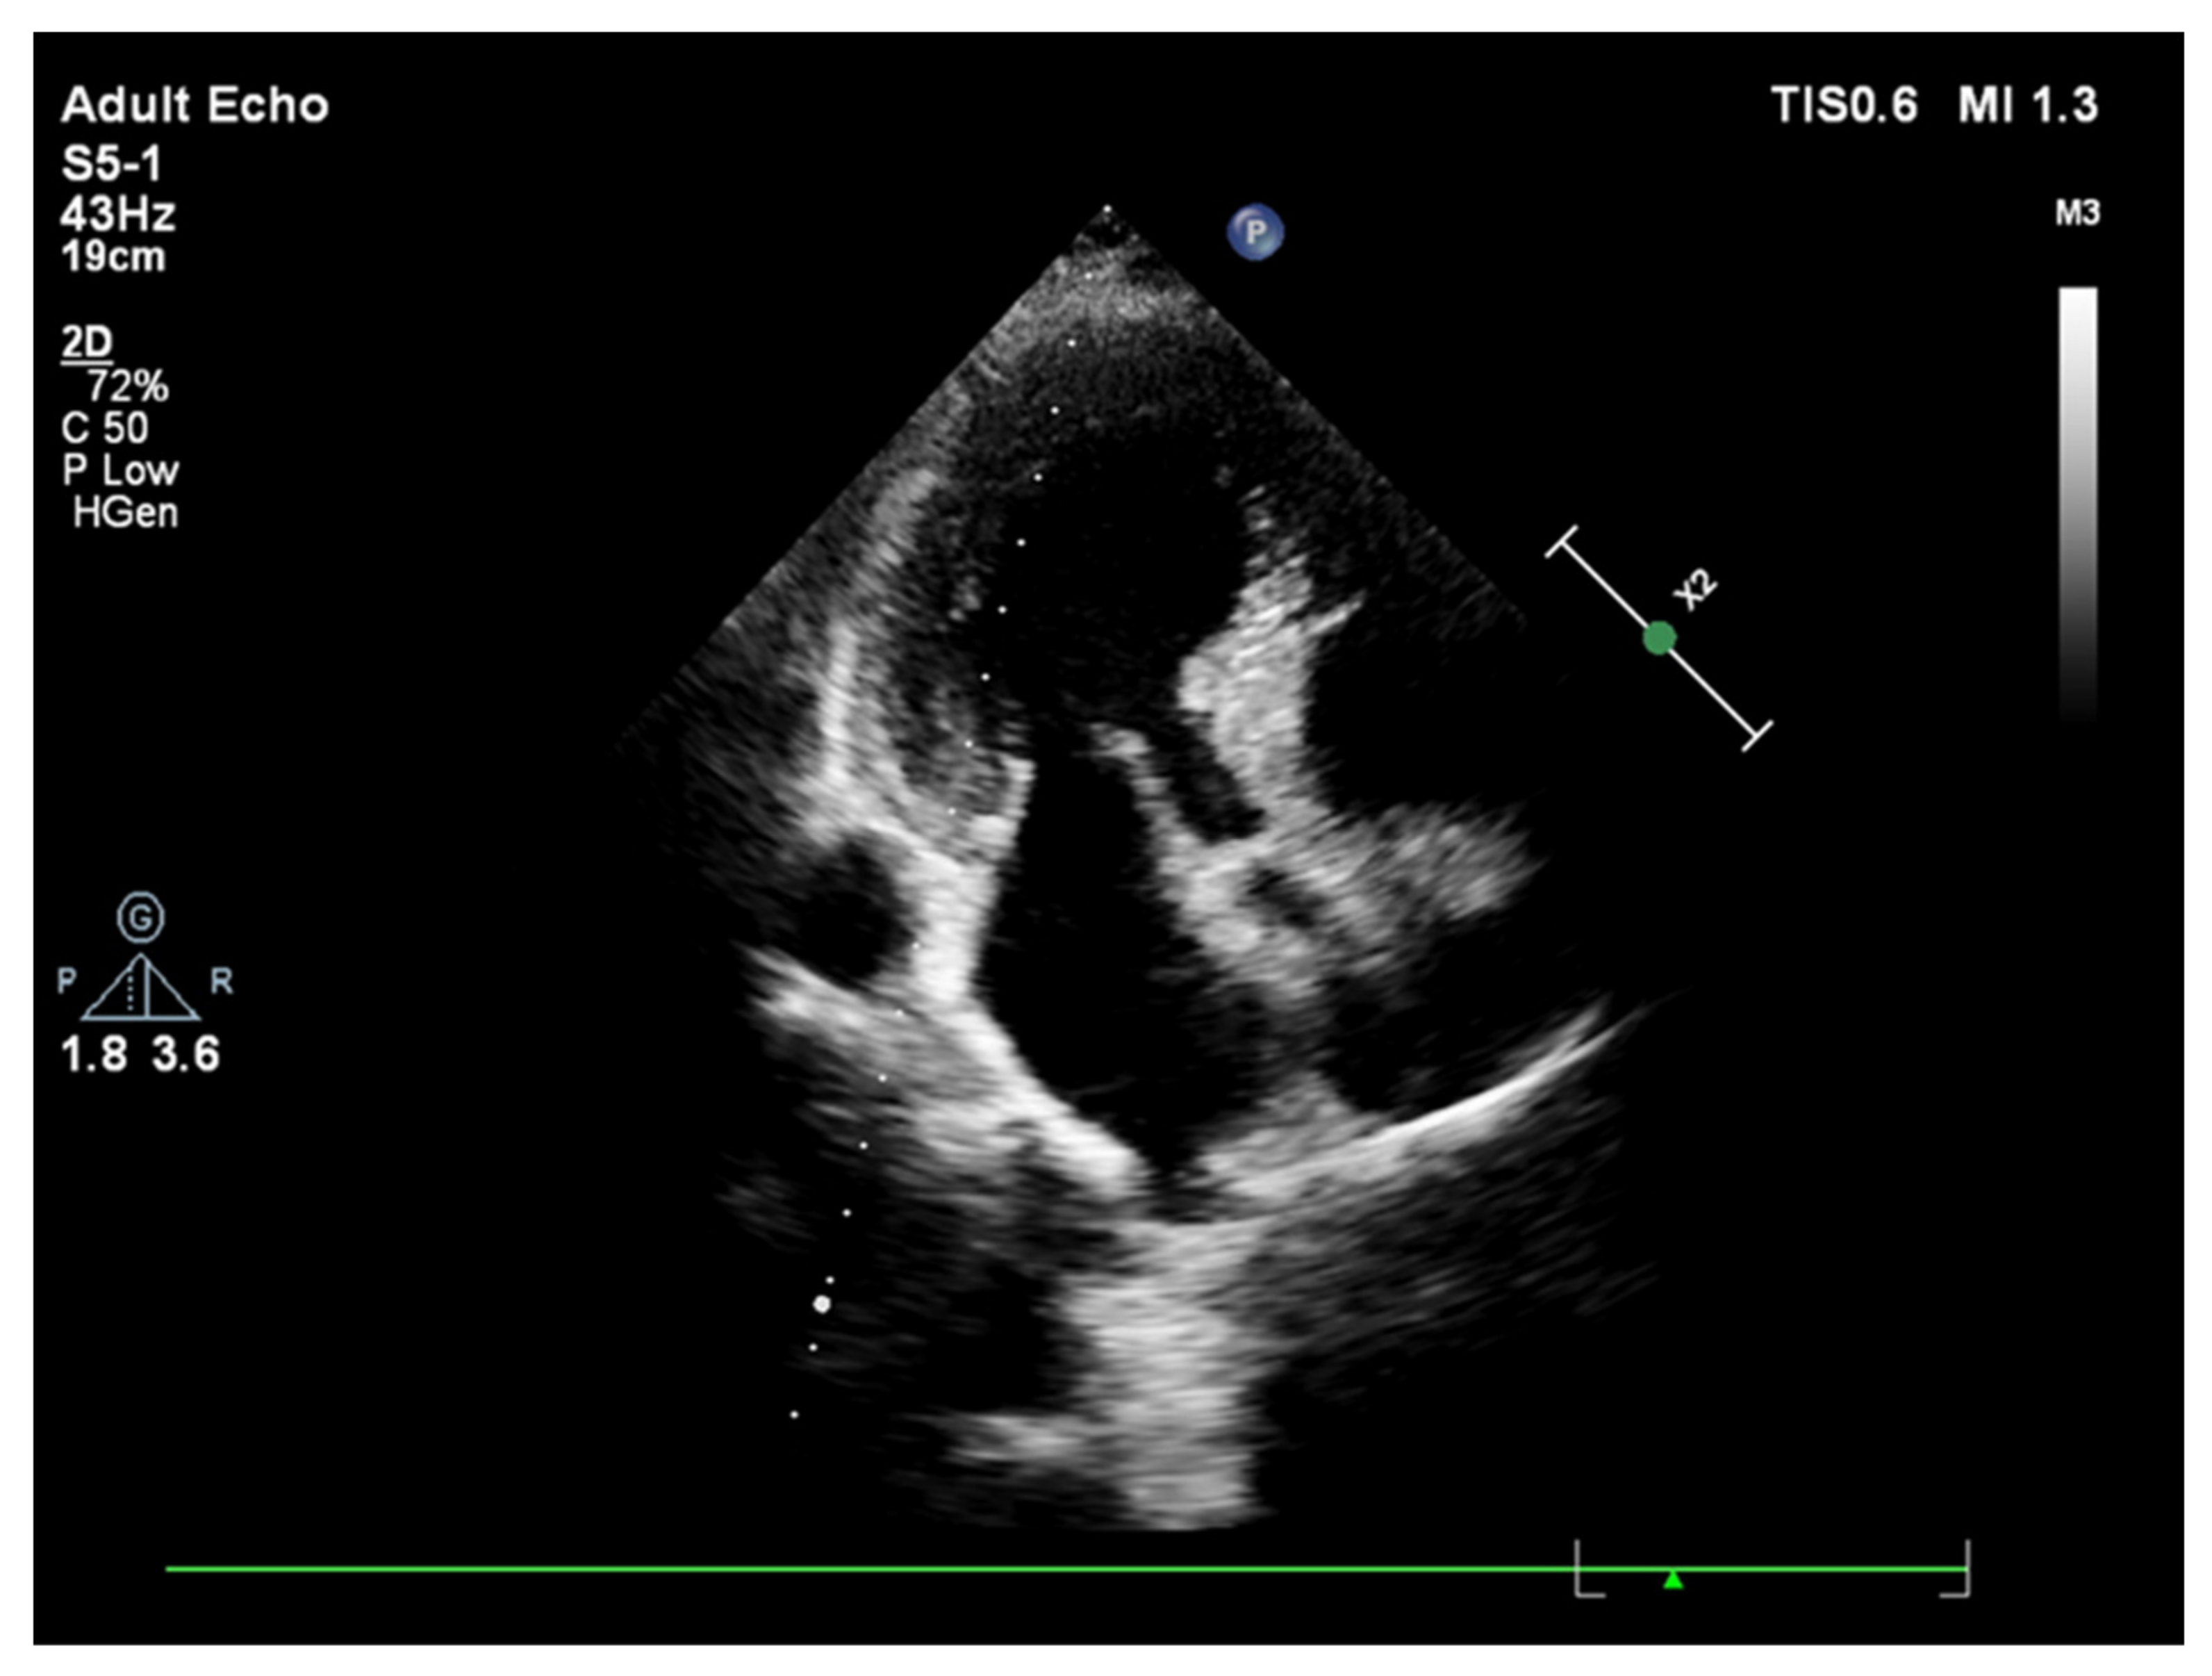

2. Basal Septal Hypertrophy and Clinic Observations

- Yalçin, F.; Topaloglu, C.; Kucukler, N.; Ofgeli, M.; Abraham, T.P. Could early septal involvement in the remodeling process be related to the advance hypertensive heart disease? Int. J. Cardiol. Heart Vasc. 2015, 7, 241–245. [Google Scholar] [CrossRef] [PubMed][Green Version]